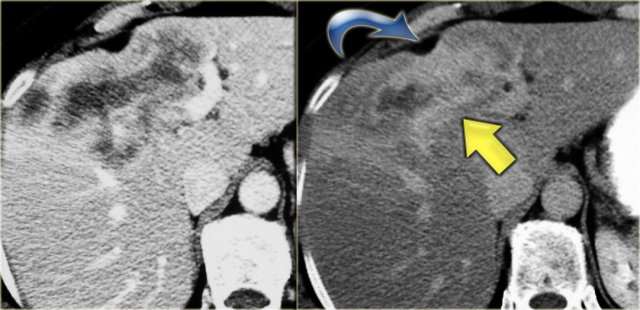

On the left a typical case.

Notice the capsular retraction (blue arrow) and the late enhancement (yellow arrow).